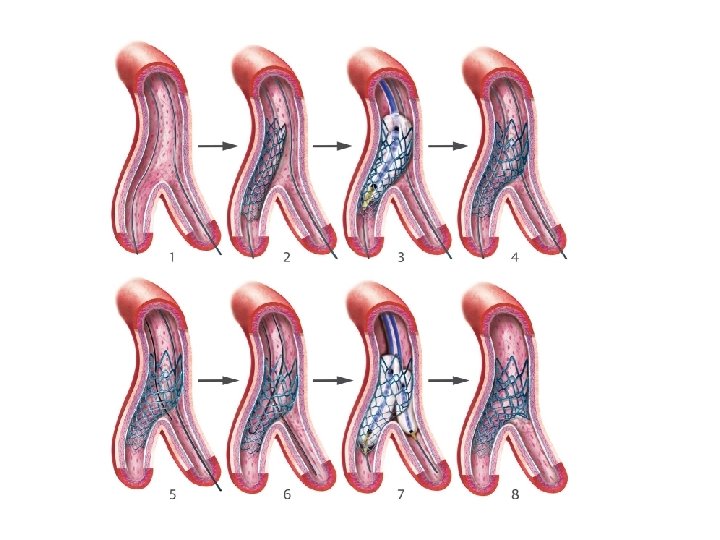

Provisional stenting strategy 1. Both branches are wired starting with the most difficult one 2. MB is stented (stent sized according to MB distal reference) and SB wire is jailed 3. The stent is post-dilated using the Proximal Optimization Technique (POT) to maximize stent apposition 4. Stent is now well apposed proximally, while the SB is partially covered by scaffolding 5. MB wire is pulled back and reinserted through the most distal strut of the SB opening scaffold 6. Jailed wire is removed and re-inserted in the distal MB (with a formed loop at the distal end) 7. The Kissing Balloon inflation is done to optimize side branch flow and access 8. Final result (if suboptimal, can then place additional stents)